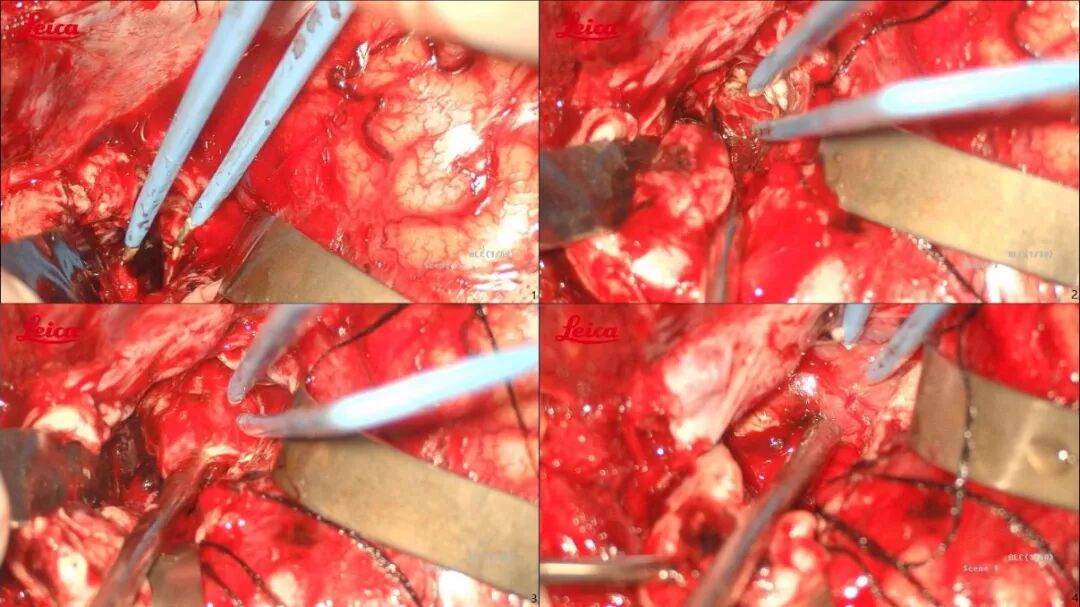

仰卧位,头偏右,取左侧额颞瓣;咬平蝶谷脊以充分暴露颅底(考虑瘘口供血动脉为颈外动脉颅底硬膜支、部分颈内动脉及侧裂动脉);为防止阻断动脉化静脉引起出血,先临时阻断可能责任供血动脉,待确定责任动脉后再将其离断,最后处理引流静脉;术中颅内压力高先清除部分血肿,动静脉瘘切除后将剩余血肿全部清除(见图3,术中截图)。因存在侧脑室及四脑室存在血肿,术中开放侧脑室,留置脑室外引流管(含压力测量)。

图3. 术中手术过程截图